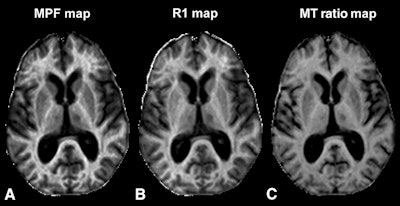

The current study included 14 healthy control subjects, 18 relapsing-remitting MS patients, and 12 secondary-progressive MS patients. The participants underwent 3-tesla MRI (Achieva, Philips Healthcare) with a transmit-receive head coil to create 3D whole-brain MPF maps to view white matter, gray matter, and MS lesions.

While myelin loss in white and gray matter in MS patients has been seen in postmortem pathological studies, this research for the first time establishes its clinical significant in gray matter, thanks to macromolecular proton fraction (MPF) mapping.

Now, the researchers have extended MPF mapping to multiple sclerosis, which is characterized by a loss of myelin, the fatty protective sheath around nerve fibers. Myelin is most abundant in the brain's white matter, but it is also found in smaller amounts in gray matter.